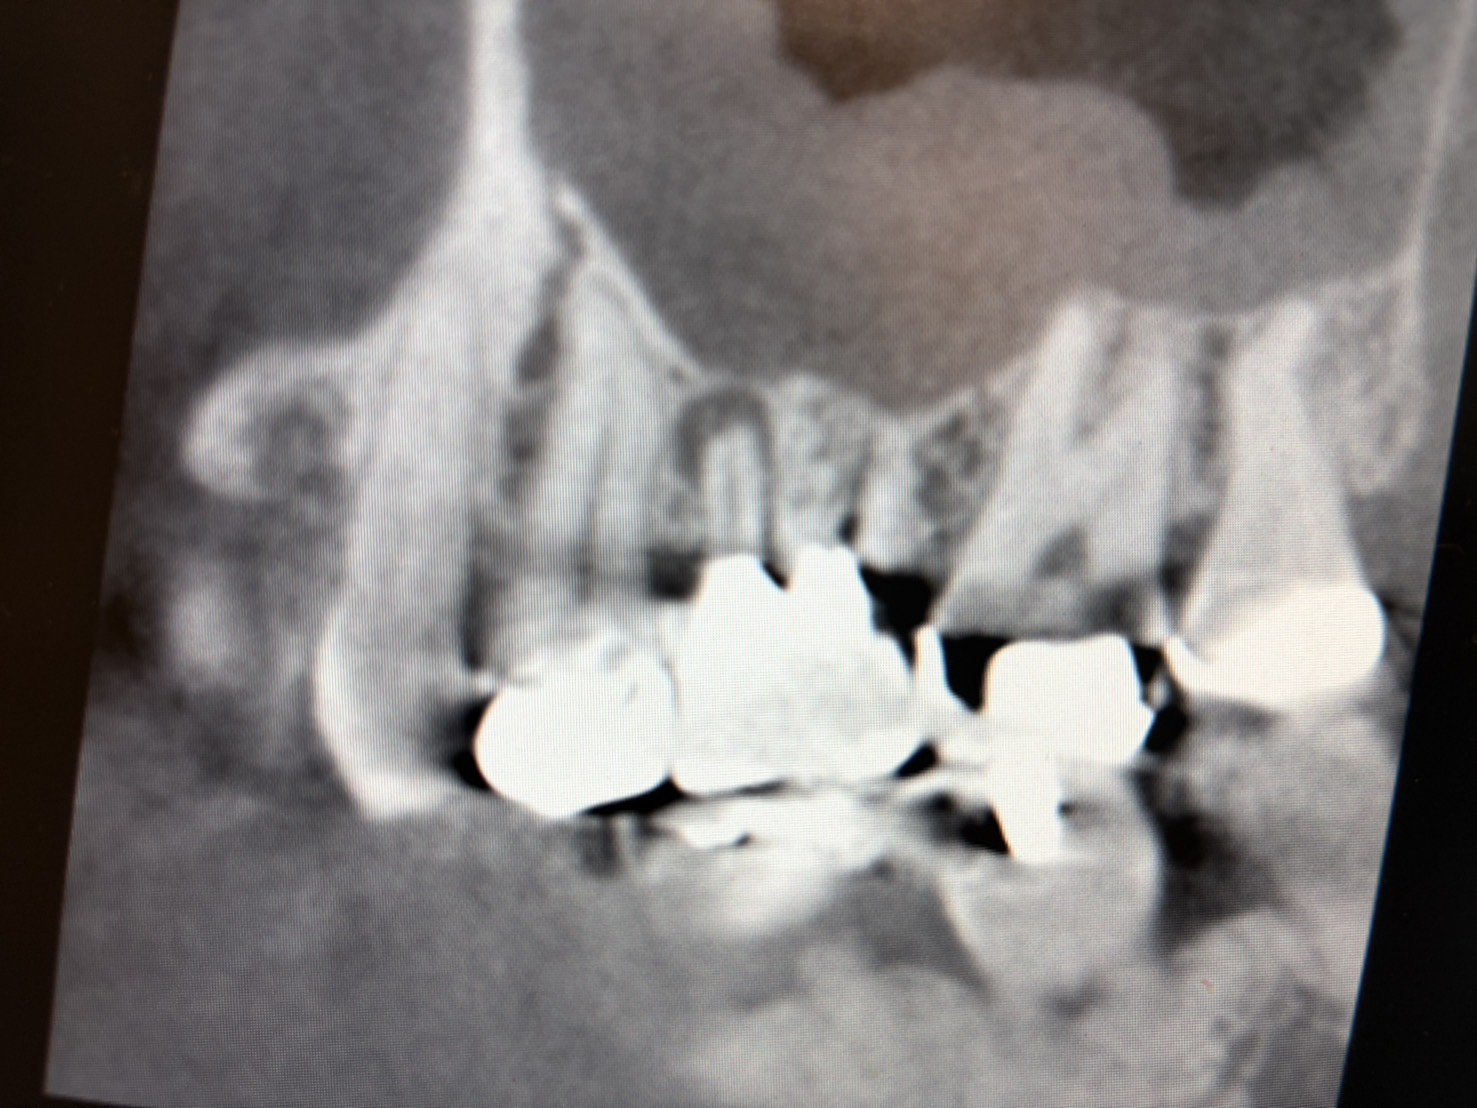

そこでCTを撮影すると、こんな画像が!!

6番目の歯に大きな根尖透過像(黒くなっている部分)が認められ、さらに上顎洞内には上顎洞粘膜の肥厚も認められます。

これにより、治療すべき歯は6番目であると確信しました。

※根尖透過像:歯の根の先に炎症があり、黒く写っている状態

※上顎洞粘膜の肥厚:上顎洞の粘膜が炎症で厚く腫れている状態

診断ができれば、あとは治療ですが、画像でもはっきりと映っているのは見落としの根管です。

本来4本治療しなければいけない根管があるのに、3本しか治療されていません。